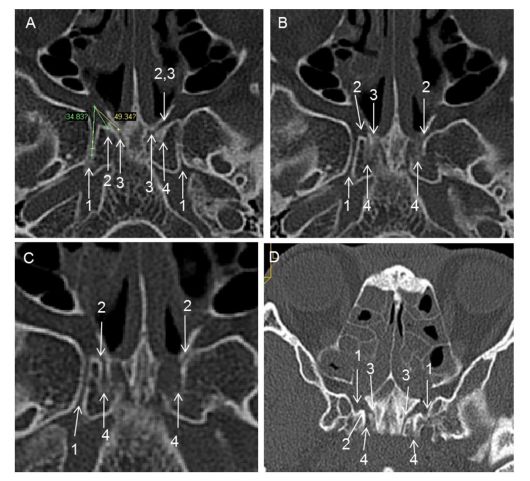

图示:1 翼管,2 腭鞘管,3 犁鞘管,4 后沟,5 蝶骨鞘突,6 犁骨,7 蝶窦开口。冠位CT的左侧2为插入探针后的腭鞘管。

图示:a、右侧腭鞘管前开口层面的轴位ct。右侧翼管与犁鞘管形成的夹角(黄线)大于翼管与腭鞘管的夹角(绿线)。腭鞘管前开口向前洞口样扩大,如果从此处往后寻找该管,很有可能会将犁鞘管误认为腭鞘管,有许多之前的文献都犯了这种错误。b、右侧腭鞘管后开口层面的轴位ct,刚好位于a图的下两个层面。可以同时看到右侧翼管、腭鞘管与犁鞘管。c、为b图的下两个层面。尽管此时左侧的后沟非典型的管样结构,但其锐利的外侧缘依然有助于定位腭鞘管。而右侧的后沟显示很清晰,平行于正中线。d、另一位患者的斜位重建显示了右侧腭鞘管全长、腭鞘管与犁鞘管间的骨性分隔、后沟。1 翼管,2 腭鞘管,3 犁鞘管,4 后沟。

图示:颅骨标本解剖及ct影像。a、右侧腭鞘管后开口层面的周围ct。右侧后沟呈一个近乎平行矢状面的管样结构。b、另一标本左侧腭鞘管后开口层面。左侧后沟往后洞口样扩大,其外侧缘锐利而清晰,大致平行矢状面。c、颅底的下面观,该标本的双侧后沟均为狭窄的沟状。d、另一例标本的下面观提示其左侧后沟呈椭圆形的窝状。e、内镜下观察左侧颅底标本,腭骨蝶突已被部分磨除,后沟与犁鞘管之间的骨性分隔清晰可见。f、完全去除腭骨蝶突,显示翼腭窝内的犁鞘管与腭鞘管。1 翼管,2 腭鞘管,3 犁鞘管,4 后沟,5 腭骨蝶突。

图示:一例已移除探针的颅骨标本的ct影像。a、腭鞘管前开口层面的冠状位重建。犁鞘管位于腭鞘管上内侧,而翼管位于此两者上方。腭鞘管前份与犁鞘管间的骨性分隔很菲薄。b、腭鞘管后开口层面的冠状位重建。这个层面时腭鞘管与犁鞘管间的骨隔相当厚。犁鞘管往上走形至蝶窦底壁。c、腭鞘管前开口层面的轴位ct。后沟的上壁可以辨认,但不足以用来定位腭鞘管。犁鞘管与腭鞘管呈斜行关系增加了区别两管的难度。可以清楚地看到左侧犁鞘管的全长,但常被误认为腭鞘管。d、腭鞘管后开口层面的的轴位ct,为c图的下两个层面。后沟近乎平行中线、呈长管状,顺其往前上方,很容易辨认出腭鞘管。e、矢状位重建。后沟与硬腭的平均夹角为17.9度,提示在平行硬腭扫描的轴位层面上更容易辨认出后沟。f、腭鞘管与硬腭平均夹角为44.85度,提示在平行硬腭扫描的轴位层面上不好辨认腭鞘管。1 翼管,2 腭鞘管,3 犁鞘管,4 后沟。